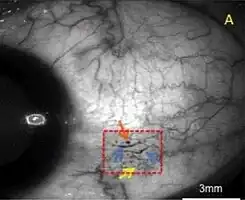

| A case of conjunctival microangiopathy (red dashed-square) secondary to diabetes demonstrating a microaneurysm (orange arrow), vessel dilatation (blue arrows), and vascular tortuosity (yellow arrow). | |